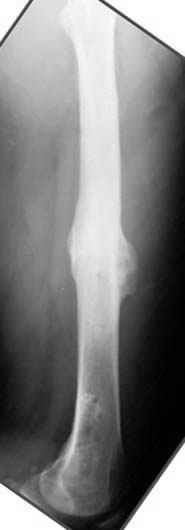

Несколько снимков из моей коллекции, чтобы разьяснить, почему мы до сих пор делаем различные варианты остеотомии.

На рисунке N1 предоперационный план лечения ложного сустава шейки бедра- линия ложного сустава, угол и направление введения импланта, клиновидная остеотомия в градусах и миллиметрах, второй снимок после коррекции, расчет, на сколько удлиняется конечность и размеры импланта;

N3 рисунок окончательный снимок, после операции моя рентгенограмма должен выглядеть примерно как эта картина. На N4 снимке клин перед удалением; N5 послеоперации 3 нед.; N6 окончательная рентгенограмма.

Djoldas Kuldjanov 23 Ноябрь 2004, 18:21

пластическая модель; и коррекция бедра аппаратом Илизарова.

хотя даже если бы и инфекция , то nail exchange с рассверливанием канала - вариант дебрайдмента) Я думаю, что последовательность развития событий:

Узкий к-м канал - тонкий гвоздь- усталостный перелом дистальных винтов - развитие нестабильности и как ее результат остеолиз вокруг гвоздя - деформация анатомической оси бедра. Похоже, что я понял почему аппарат, а не новый гвоздь:-)